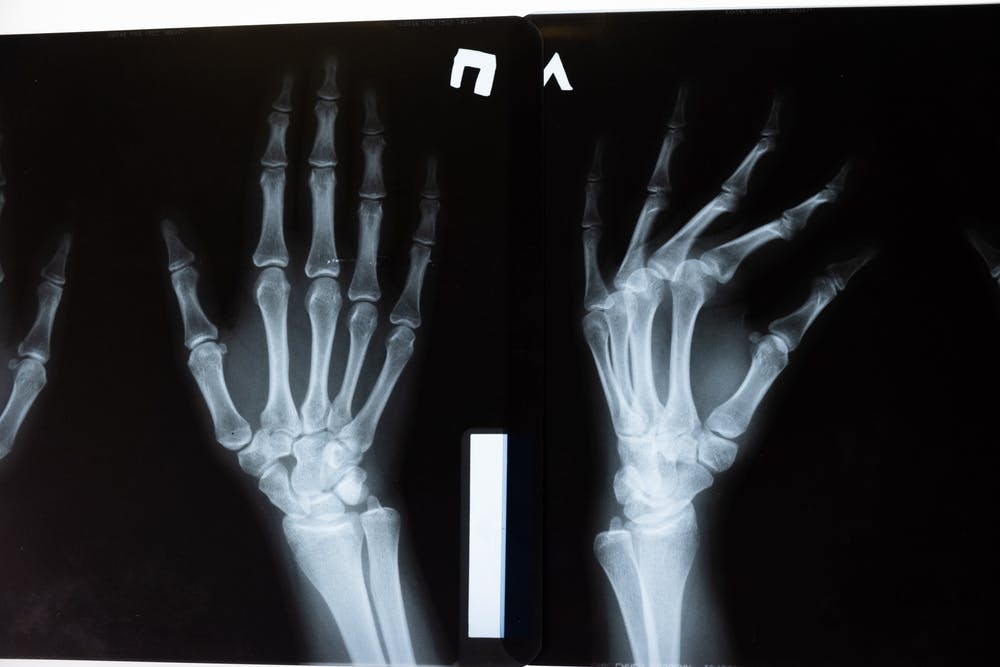

Car accidents are one of the most common causes of broken bones and fractures. The tremendous force that your body needs to absorb will cause your bones to break.

The severity of the damage depends on the location of the break and the impact of the collision.

The most common body parts affected are the hands, arms, feet and legs. Such injuries will require surgery, framing, implants, casting, physical therapy or a combination of treatments.